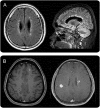

Figure 3. Optic nerve MRI lesions characteristic of neuromyelitis optica spectrum disorder

(A) Dense gadolinium-enhancing lesion at the posterior part of the right optic nerve. (B) Extensive gadolinium-enhancing lesion at the bilateral posterior part of the optic nerve/chiasm.

Figure 4. Spinal cord MRI lesions characteristic of neuromyelitis optica spectrum disorder

(A) Longitudinally extensive cord lesion involving thoracic cord. (B) Exclusive involvement of gray matter (H-shaped cord lesion).